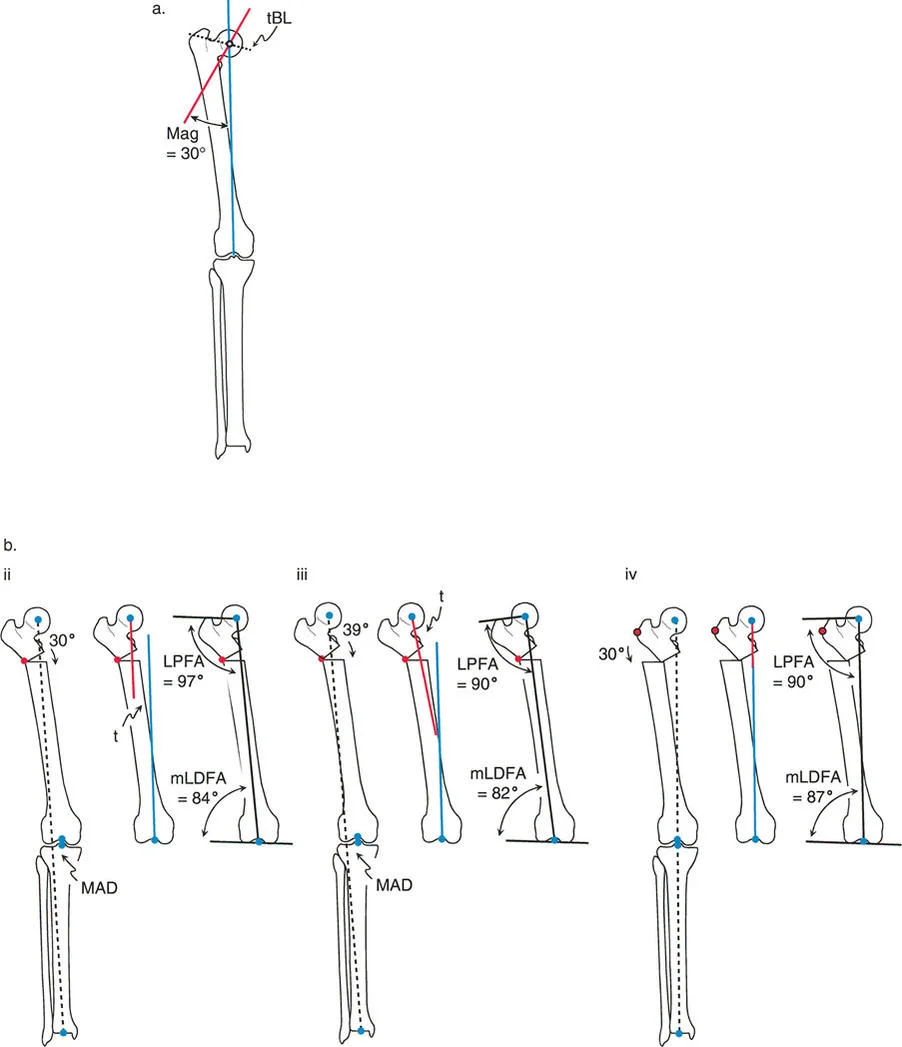

* تحديد المحور الميكانيكي: رسم الخطوط التي تحدد المحور الميكانيكي للطرف بدقة.

* قياس الزوايا: قياس الزوايا المختلفة للمفاصل (مثل زاوية الفخذ الوحشية القريبة mLPFA وزاوية الفخذ الوحشية البعيدة mLDFA) ومقارنتها بالقيم الطبيعية.

* تحديد موقع مركز دوران الانحراف (CORA): وهو نقطة التقاطع بين محاور العظم القريبة والبعيدة، والتي تمثل قلب التشوه.

مركز دوران الانحراف (CORA)

يعتبر CORA خاصية أساسية للتشوه في العظم. يُعرّف بأنه نقطة تقاطع خط المحور الميكانيكي (أو التشريحي) القريب وخط المحور الميكانيكي (أو التشريحي) البعيد.

* CORA الحقيقي: هو القمة التشريحية الفعلية للتشوه.

* CORA الحل (Resolution CORA): نقطة نظرية تُستخدم في التشوهات متعددة المستويات حيث تتقاطع المحاور القريبة والبعيدة النهائية، وقد لا تقع هذه النقطة داخل العظم نفسه.

بينما يعتبر CORA حقيقة تشريحية ثابتة، فإن ACA يقع جزئيًا تحت سيطرة الجراح. يمثل ACA النقطة المحورية التي يدور حولها الجزء البعيد من العظم لتحقيق التصحيح.

* الموضع الأمثل: يجب أن يكون ACA موجهًا بشكل عمودي على مستوى التشوه ويمر مباشرة عبر CORA.

مستوى قطع العظم (Osteotomy Level)

مستوى قطع العظم (الشق الجراحي) يقع بالكامل تحت سيطرة الجراح. تحدد العلاقة الهندسية بين مستوى قطع العظم، وACA، وCORA النوع الدقيق للتصحيح الناتج، وتحدد ما إذا كان سيحدث تشوه ثانوي غير مقصود (مثل الانزياح غير المرغوب فيه).

القاعدة الذهبية الأولى: القطع والمفصلة عند مركز الانحراف

عندما يمر كل من قطع العظم وACA مباشرة عبر CORA، يتم تصحيح التشوه الزاوي بشكل مثالي. يتم استعادة المحور الميكانيكي، ولا يوجد انحراف في المحور الميكانيكي (MAD)، وتبقى أجزاء العظم القريبة والبعيدة متوازية تمامًا. هذا هو السيناريو المثالي، والذي غالبًا ما يتحقق بقطع عظم وتدي بسيط (فتح أو إغلاق) عند قمة التشوه.

القاعدة الذهبية الثانية: المفصلة عند مركز الانحراف والقطع بمستوى مختلف

في بعض الأحيان، قد يكون قطع العظم مباشرة عند CORA غير ممكن سريريًا بسبب سوء حالة الجلد، أو وجود أدوات جراحية سابقة، أو مشاكل في جودة العظم في منطقة الكردوس/الجذع. إذا بقي ACA عند CORA، ولكن تم إجراء قطع العظم عند مستوى مختلف (أقرب أو أبعد عن CORA)، فسيتم تصحيح التشوه الزاوي بالكامل. ومع ذلك، ستنزاح نهايات العظم عند موقع قطع العظم بالنسبة لبعضها البعض.

* النتيجة السريرية: يؤدي هذا إلى "نتوء" أو تعرج في المحور التشريحي، لكن المحور الميكانيكي العام وتوجيه المفصل يظلان متوائمين تمامًا.